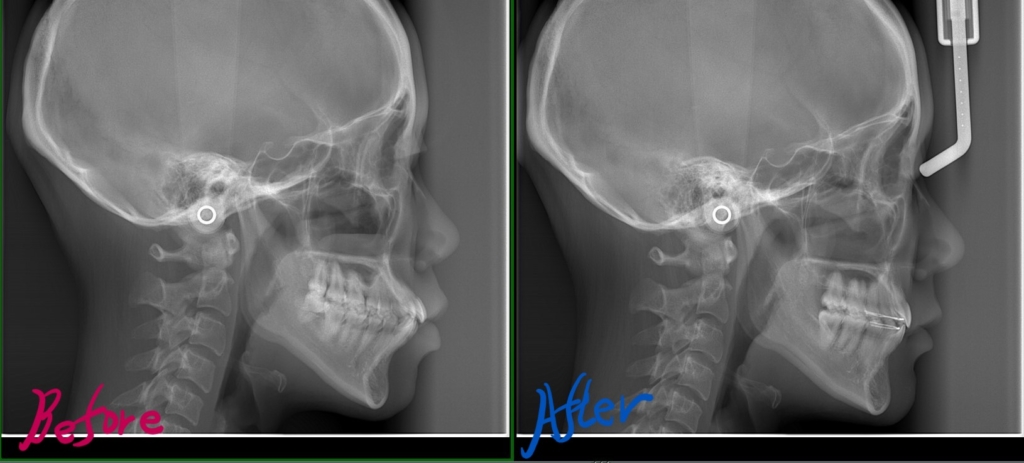

【Before】

レントゲン写真で確認すると、

この患者さんの場合、

【After】

矯正後の状態をレントゲン写真で確認すると、

参考までに矯正治療前後の歯並びや横顔・口元、レントゲン写真を比較してみましょう。

最後に、レントゲン写真です

その変化をレントゲン写真で追ってみましょう。